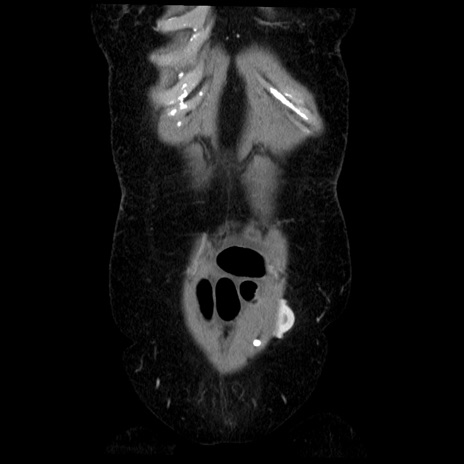

横断像